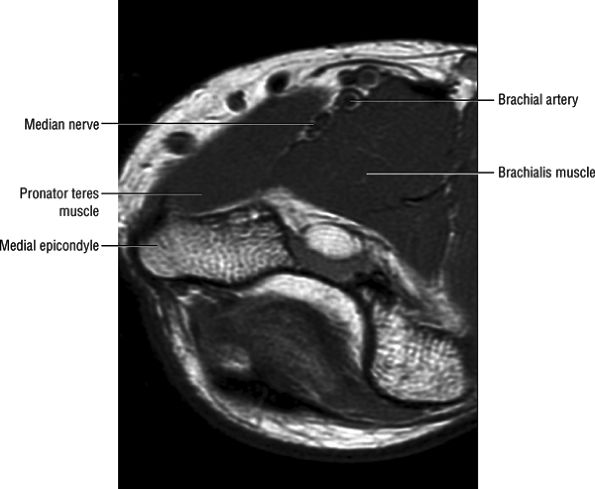

FIGURE 12.16 ● Normal MR anatomy of the median nerve. Axial PD-weighted image demonstrates the median nerve between the pronator and the brachialis muscles.

|